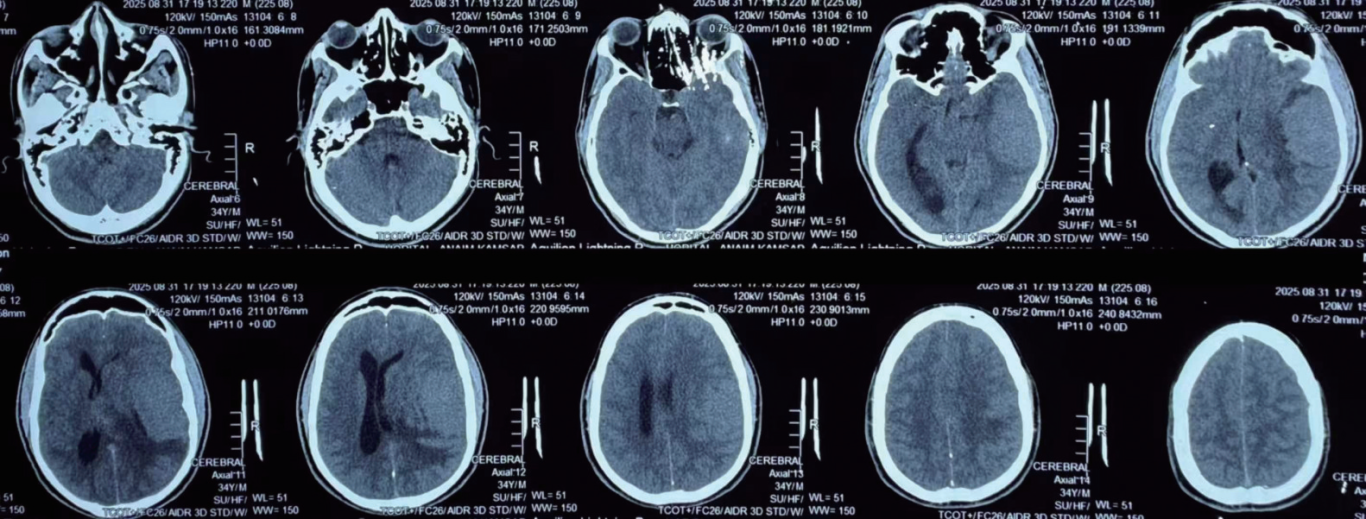

外院头颅CT平扫(图1)显示:左侧额颞顶巨大占位性病变,伴有病变周围明显脑水肿,左侧大脑半球局部脑组织及左侧侧脑室受压明显,中线结构移位。

图1 术前头颅CT显示:左侧额颞顶巨大占位性病变,伴有明显脑水肿

入院后行头颅磁共振成像(MRI)增强扫描(图2)显示:左侧额颞顶巨大占位性病变,以左侧颞叶为主,累及额叶和顶叶,局部脑组织及侧脑室明显受压移位,病变边界尚清楚,大小约7 cm × 6 cm × 4 cm,血供丰富,尤其是病变深部供血极为丰富。

图2 术前头颅MRI增强扫描所见